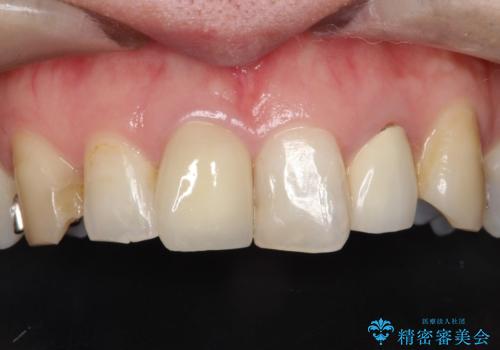

形態も色調もまわりの歯とは、調和がとれておらず、目立っていました。

今回治療することで、自然な前歯になったと喜んでいただけました。